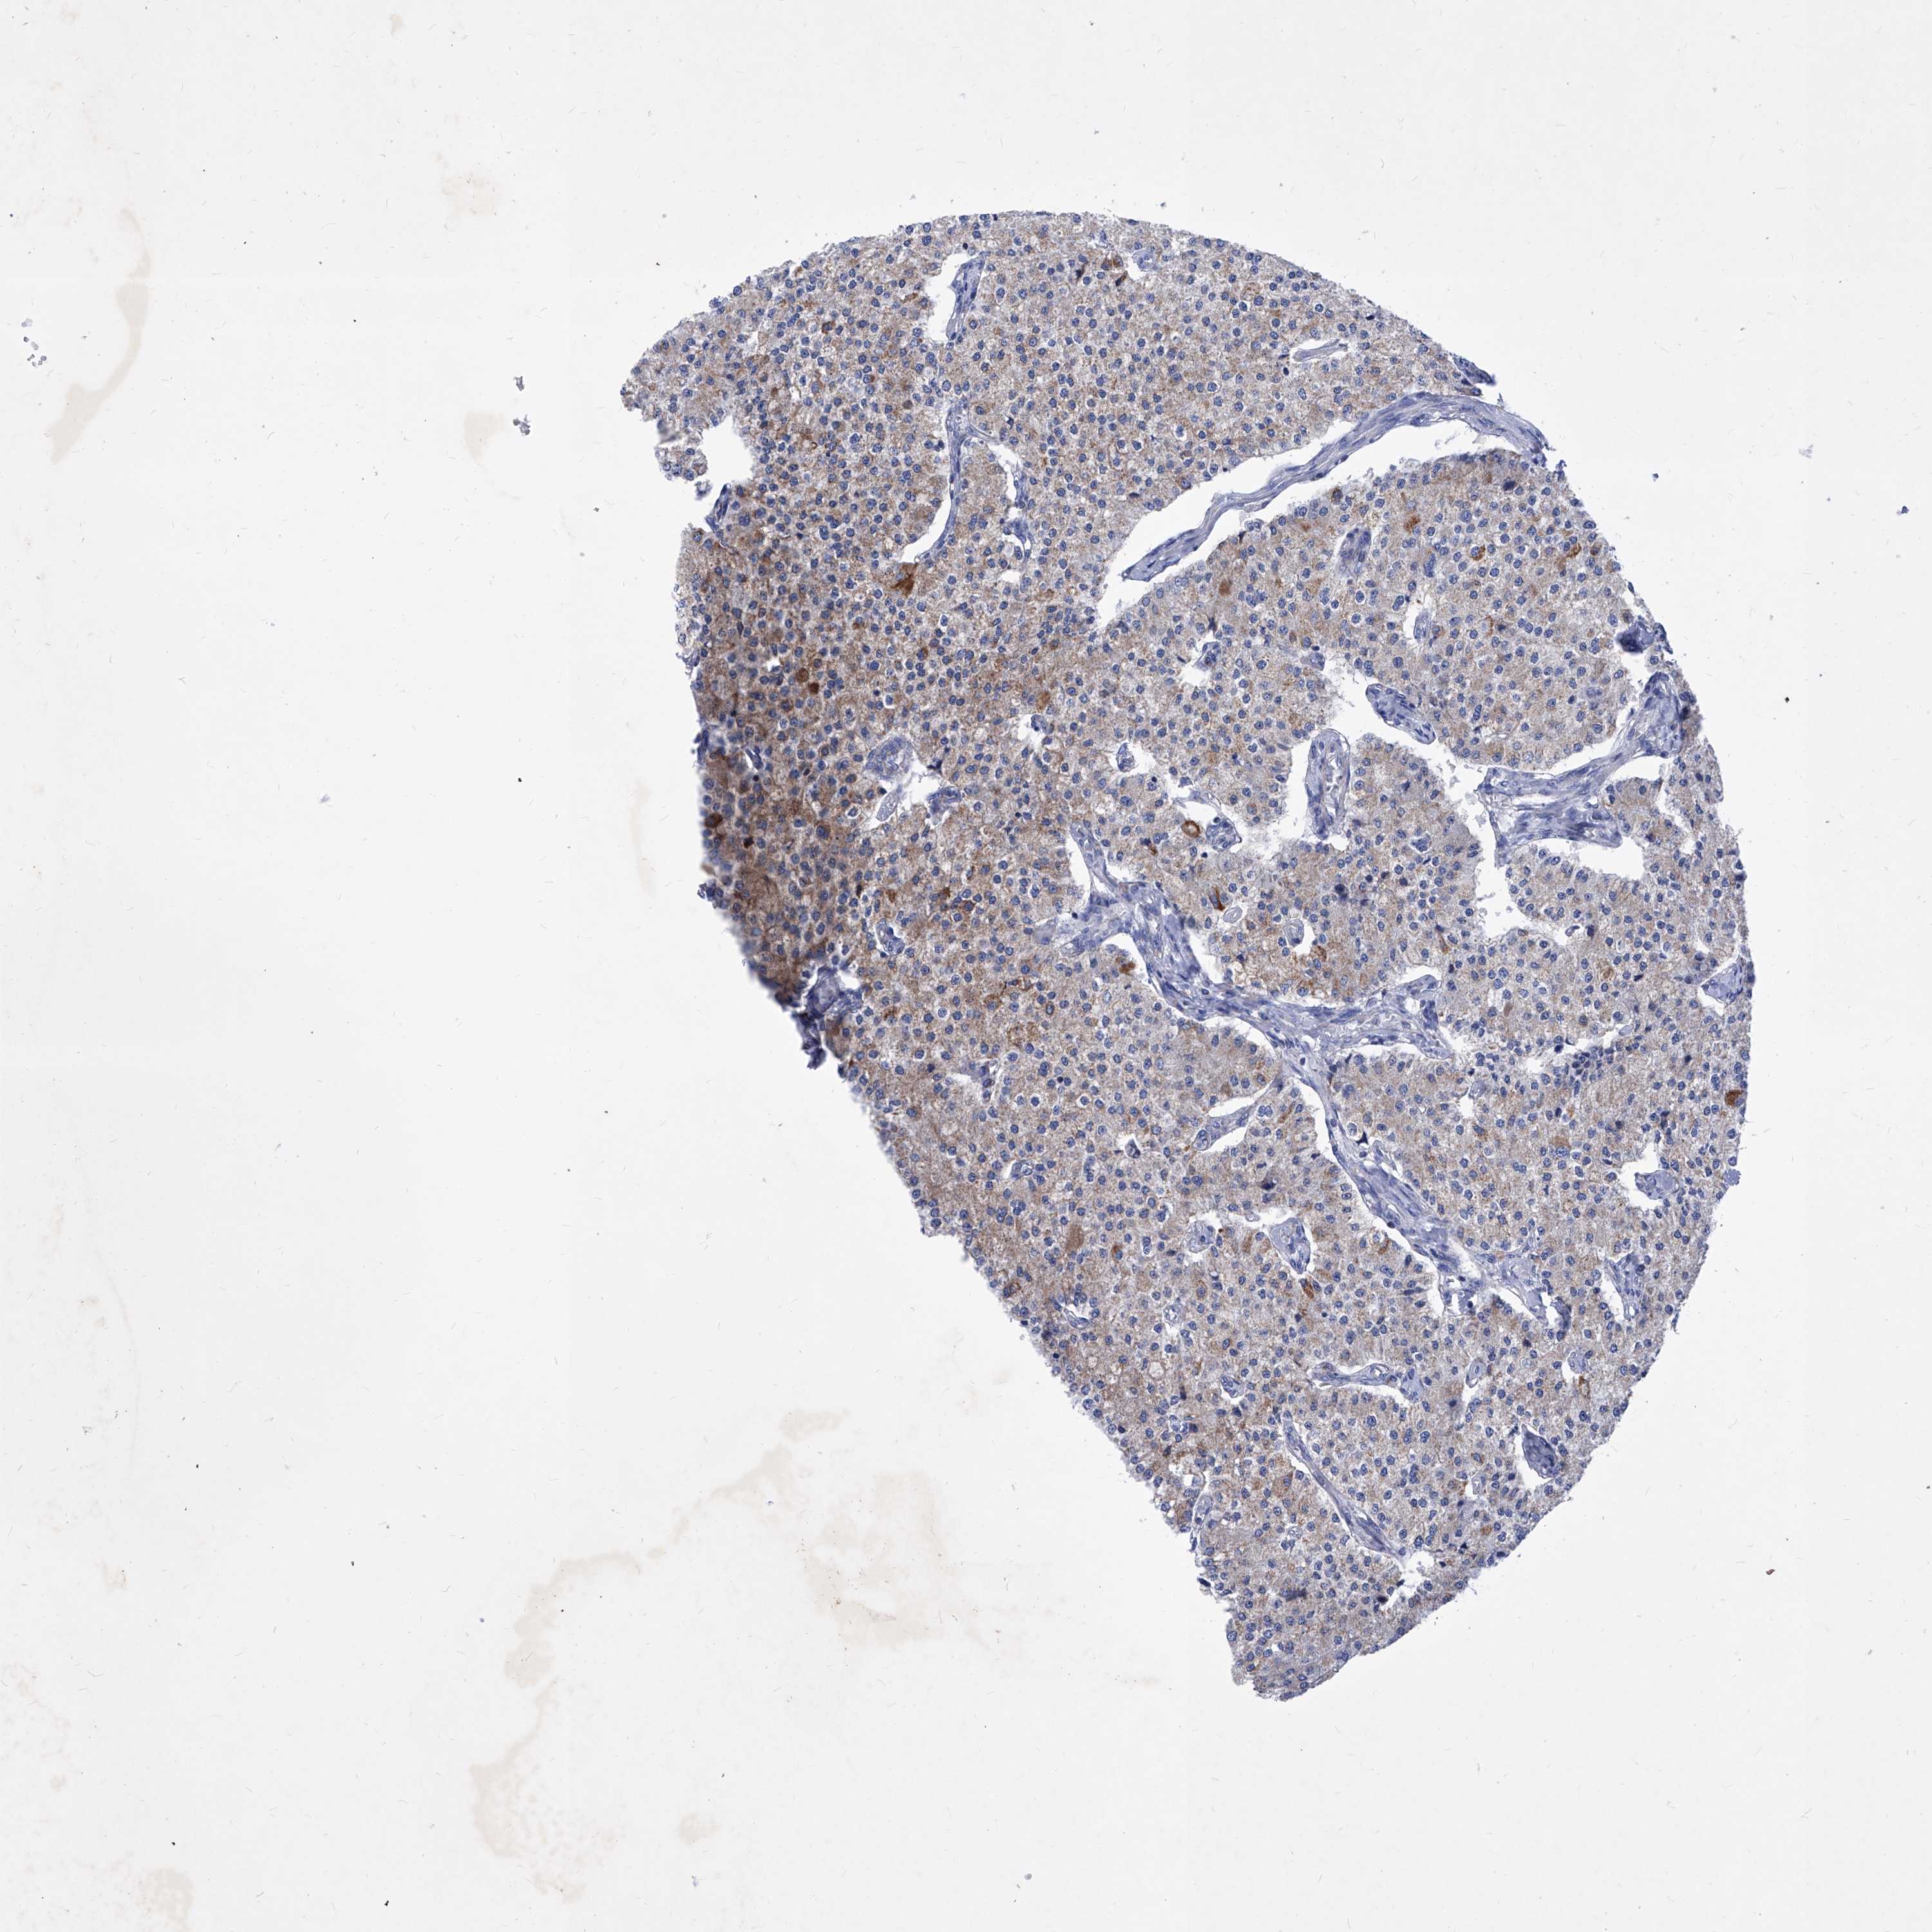

CARCINOID - Protein expressioni

A mouse-over function shows sample information and annotation data. Click on an image to view it in a full screen mode. Samples can be filtered based on level of antibody staining by selecting one or several of the following categories: high, medium, low and not detected. The assay and annotation is described here.

Antibody stainingi

Antibody staining in the annotated cell types in the current human tissue is reported as not detected, low, medium, or high, based on conventional immunohistochemistry profiling in selected tissues. This score is based on the combination of the staining intensity and fraction of stained cells.

Each image is clickable and will lead to virtual microscopy that enables deeper exploration of all samples and also displays staining intensity scores, fraction scores and subcellular localization as well as patient and tissue information for each sample.

Antibody HPA031469

Staining

High

Medium

Low

Not detected

Intensity

Strong

Moderate

Weak

Negative

Quantity

>75%

75%-25%

<25%

None

Location

Nuclear

Cytoplasmic/membranous

Cytoplasmic/membranous,nuclear

Carcinoid, malignant, NOS

Carcinoma, NOS